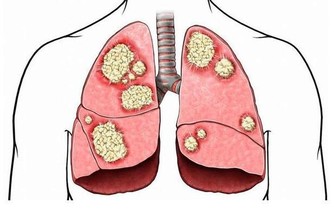

03.阿司匹林還能用來預防心腦血管疾病嗎?

最近幾年來隨著國際上的幾個大型臨床研究,結果顯示,越來越多的指南和政局認為使用阿司匹林來預防心腦血管疾病需要慎之又慎,

至於要看一個人到底能不能用,還是需要看收益和風險誰更大一些,阿司匹林用於疾病的預防,主要好處是能夠減少非致死性缺血事件,

主要風險是來自於顯著增加非致死性大出血的事件,其中包括胃腸道出血和顱內出血等等。

所以對於阿司匹林到底能不能夠預防心腦血管疾病的發生這件事情上